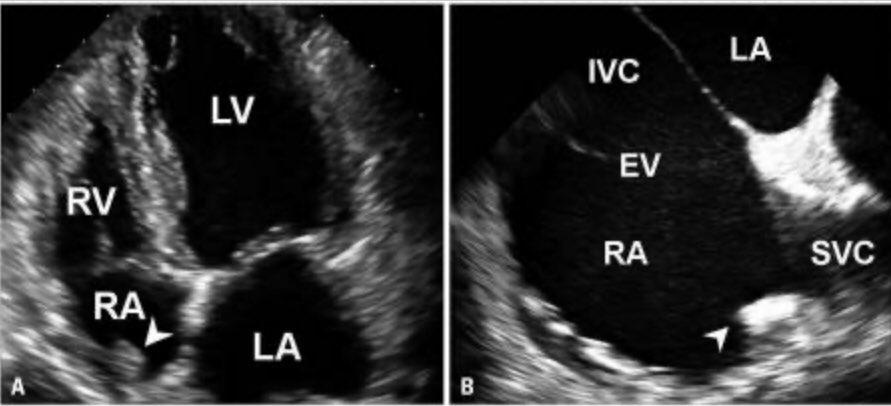

Chiari network

A: A4C

B: RV Inflow

From: ncbi.nlm.nih.gov